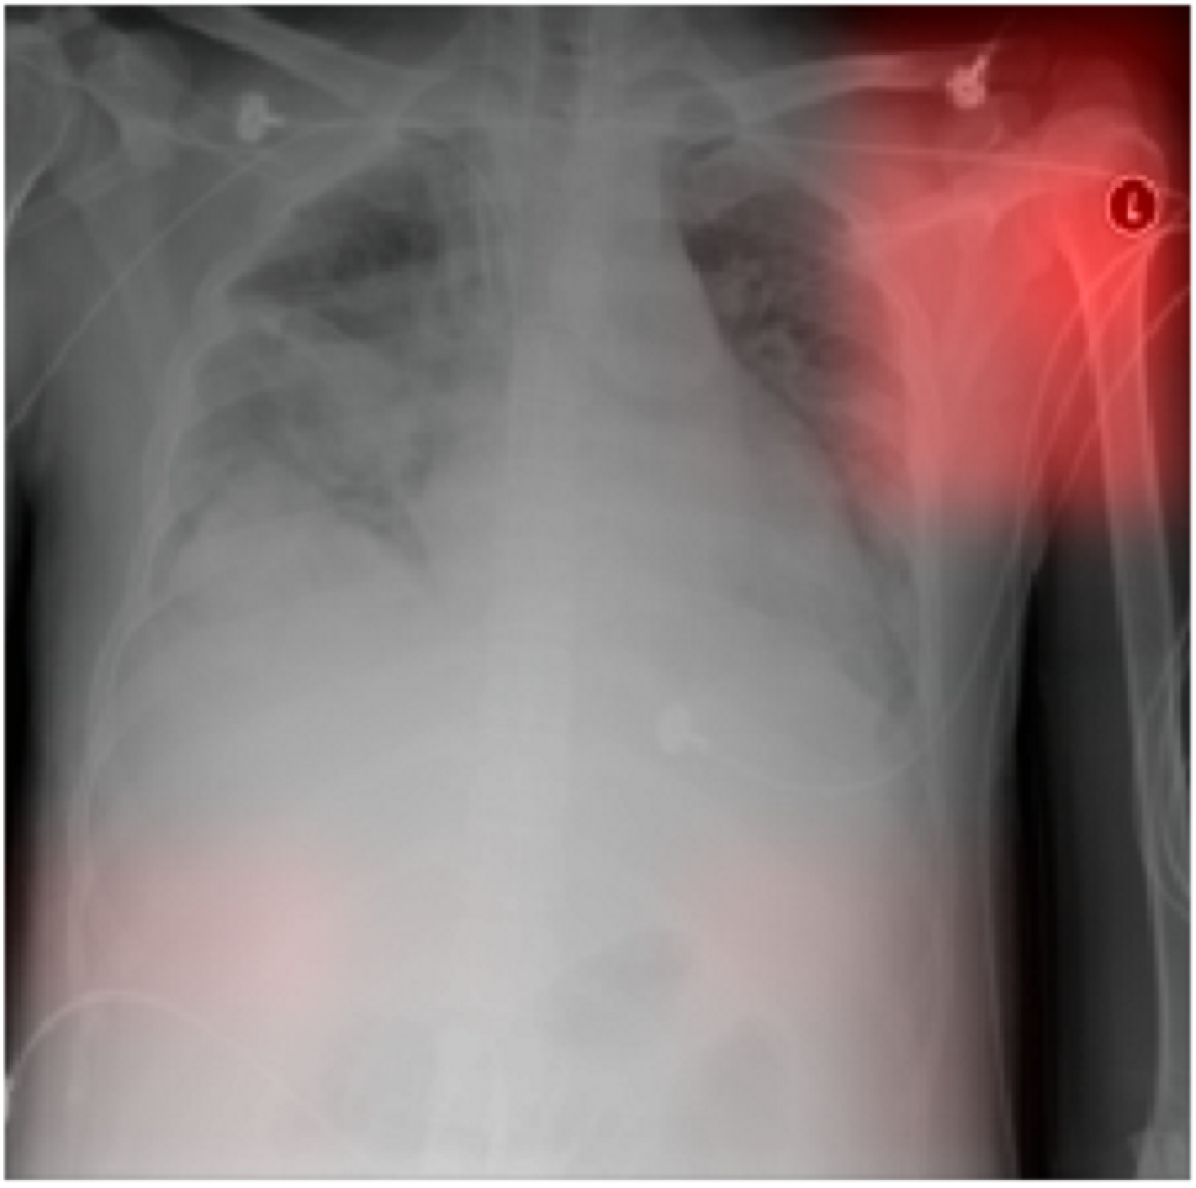

A CNN trained to identify hospital system accurately identified 22,050/22,062 (99.95%) of NIH, 8,386/8,388 (99.98%) of MSH, and 737/771 (95.59%) of IU test radiographs. To identify radiographs originating from a specific hospital system, such as NIH, CNNs used features from many different image regions (Figure  4(a)); the majority of image subregions were individually able to predict the hospital system with >= 95% certainty (35.7 / 49, 72.9%, min 21, max 49, N = 100 NIH radiographs). Laterality labels were particularly influential (Figure  4(b)-4(c)).

Fig 4: CNN to predict hospital system detected both general and specific image features. (4(a)) We obtained activation heatmaps from our trained model and averaged over a sample of images to reveal which subregions tended to contribute to a hospital system classification decision. Many different subregions strongly predicted the correct hospital system, with especially strong contributions from image corners. (4(b)-4(c)) On individual images, which have been normalized to highlight only the most influential regions and not all those that contributed to a positive classification, we note that the CNN has learned to detect a metal token that radiology technicians place on the patient in the corner of the image field of view at the time they capture the image. When these strong features are correlated with disease prevalence, models can leverage them to indirectly predict disease.